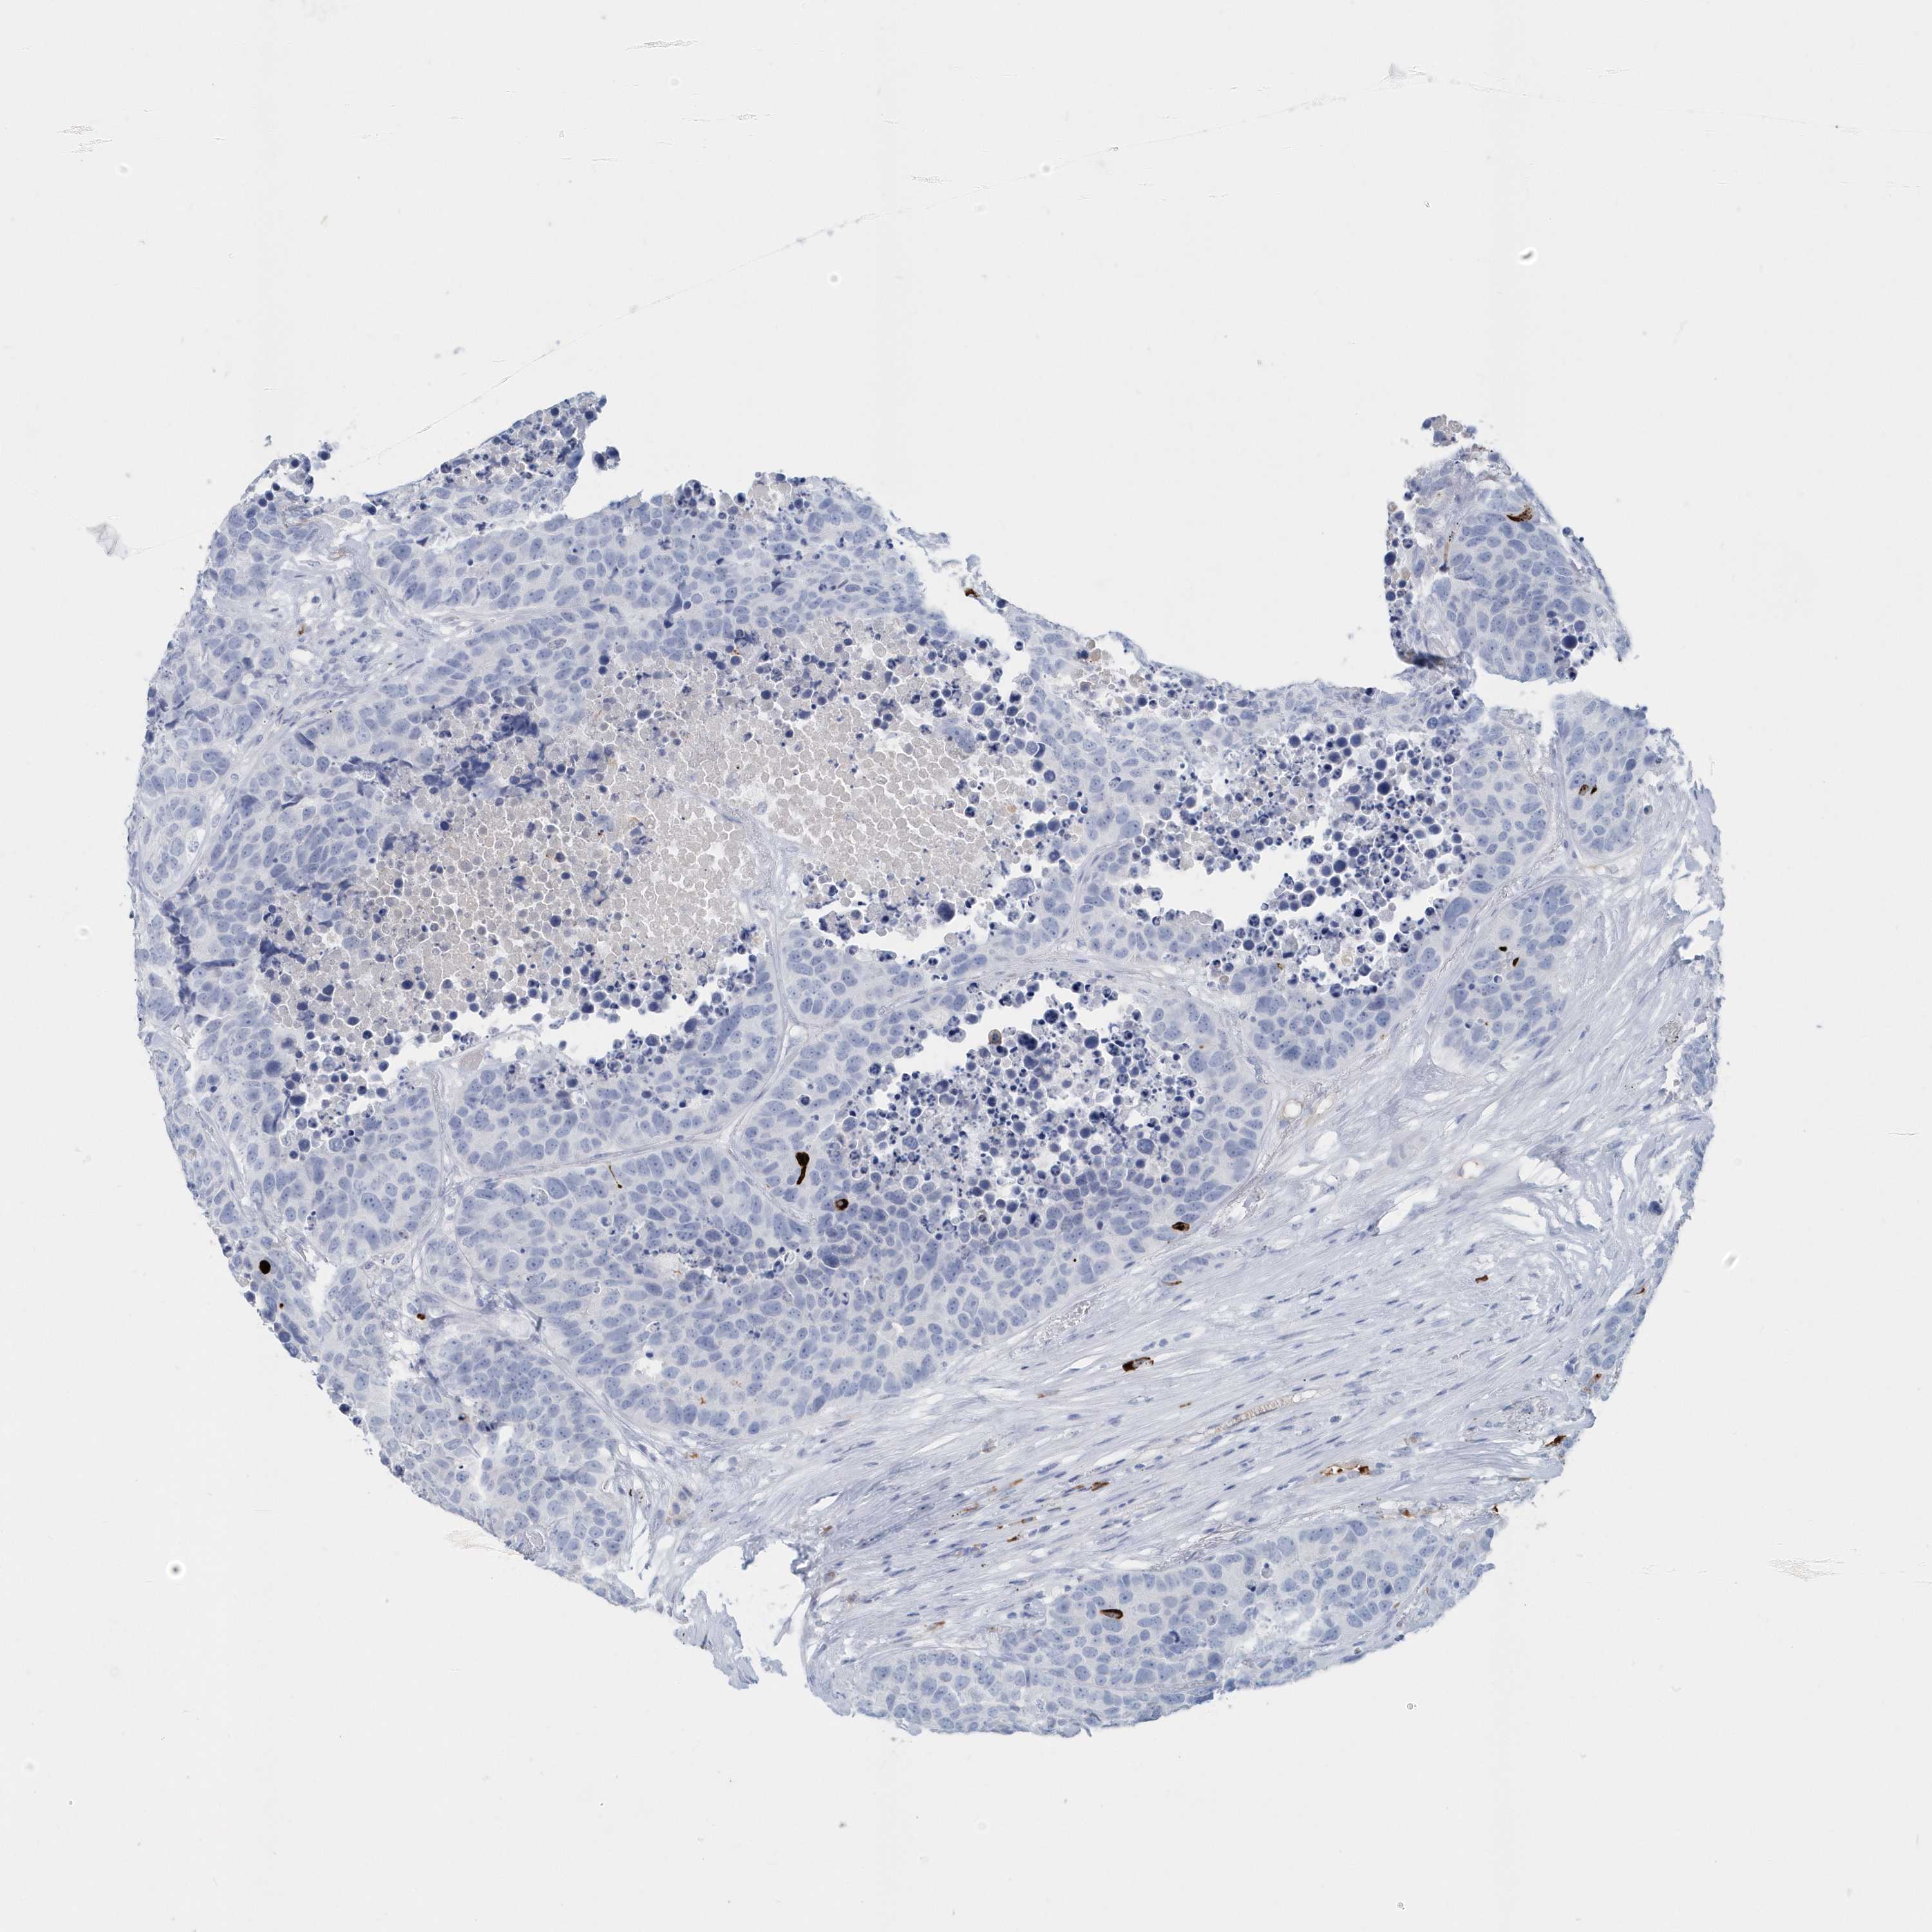

CARCINOID - Protein expressioni

A mouse-over function shows sample information and annotation data. Click on an image to view it in a full screen mode. Samples can be filtered based on level of antibody staining by selecting one or several of the following categories: high, medium, low and not detected. The assay and annotation is described here.

Antibody stainingi

Antibody staining in the annotated cell types in the current human tissue is reported as not detected, low, medium, or high, based on conventional immunohistochemistry profiling in selected tissues. This score is based on the combination of the staining intensity and fraction of stained cells.

Each image is clickable and will lead to virtual microscopy that enables deeper exploration of all samples and also displays staining intensity scores, fraction scores and subcellular localization as well as patient and tissue information for each sample.

Antibody HPA044132

Antibody CAB034436

Carcinoid, malignant, NOS